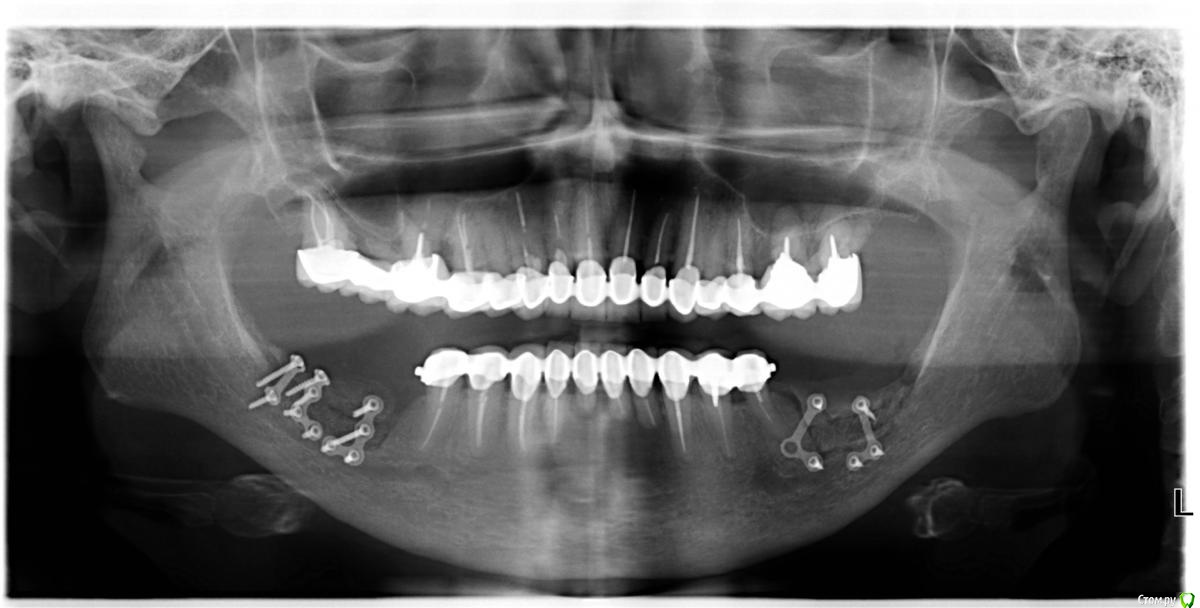

an_ver Опубликовано 17 января, 2016 Поделиться Опубликовано 17 января, 2016 (изменено) Верхние винты насквозь через SP и в свою кость? Как горизонтальный распил делаете, пальцем с язычной, тактильно? Пилите УЗ?И есть ли снимок до? Изменено 17 января, 2016 пользователем an_ver Ссылка на комментарий

Глеб Митрофанов Опубликовано 19 января, 2016 Автор Поделиться Опубликовано 19 января, 2016 Верхние винты насквозь через SP и в свою кость? Как горизонтальный распил делаете, пальцем с язычной, тактильно? Пилите УЗ?И есть ли снимок до?Верхние винты в свою кость , распил делал УЗ , язычно контроль пальпаторно , да и чувствуется , что прошёл язычную кортикалку . Снимок до конечно есть . Ссылка на комментарий

Глеб Митрофанов Опубликовано 19 января, 2016 Автор Поделиться Опубликовано 19 января, 2016 метод костных блоков с ветви здесь не рассматривали?Блоки с ветви в виде окклюзионной накладки не рассматривал , был опыт их использования , через 1,5 года эксплуатации имплантов с коронками , блоки "растаяли" , как сахар в воде 1 Ссылка на комментарий